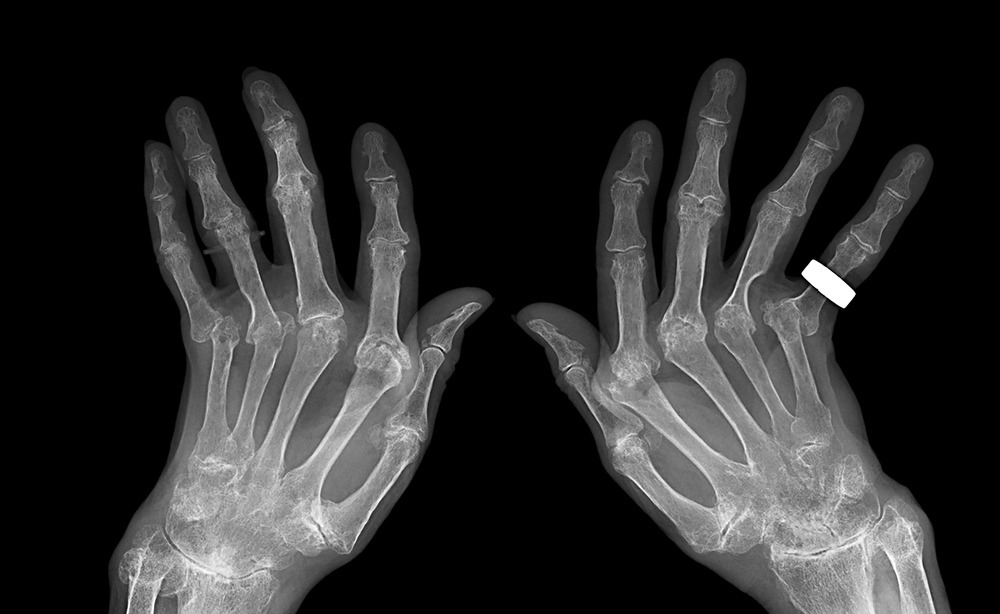

▶ 퇴행성 관절염

나이가 들어감에 따라 노화가 되면서 자연스럽게 손가락 관절이 퇴행성 변화를 일으킬 수 있습니다. 손가락 연골이 닳고 염증이 생기면서 관절염이 생길 경우 손가락 마디 통증이 발생할 수 있습니다. 마치 나이가 드신 분들이 무릎 관절에 퇴행성 변화로 인한 관절염으로 고생하시는 것과 마찬가지입니다.

이 경우 특히 손가락 첫마디 관절 쪽에서 통증을 느끼는 경우가 많습니다. 퇴행성 관절염으로 인한 손가락 통증 증상을 그대로 방치하여 시간이 오래갈 경우 손가락 관절에 변형이 찾아와 손가락 마디가 튀어 올라올 수 있습니다.